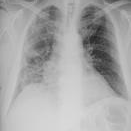

The COVID-19 disease was first discovered in Wuhan, China, and spread quickly worldwide. After the COVID-19 pandemic, many researchers have begun to identify a way to diagnose the COVID-19 using chest X-ray images. The early diagnosis of this disease can significantly impact the treatment process. In this article, we propose a new technique that is faster and more accurate than the other methods reported in the literature. The proposed method uses a combination of DenseNet169 and MobileNet Deep Neural Networks to extract the features of the patient's X-ray images. Using the univariate feature selection algorithm, we refined the features for the most important ones. Then we applied the selected features as input to the LightGBM (Light Gradient Boosting Machine) algorithm for classification. To assess the effectiveness of the proposed method, the ChestX-ray8 dataset, which includes 1125 X-ray images of the patient's chest, was used. The proposed method achieved 98.54% and 91.11% accuracies in the two-class (COVID-19, Healthy) and multi-class (COVID-19, Healthy, Pneumonia) classification problems, respectively. It is worth mentioning that we have used Gradient-weighted Class Activation Mapping (Grad-CAM) for further analysis.